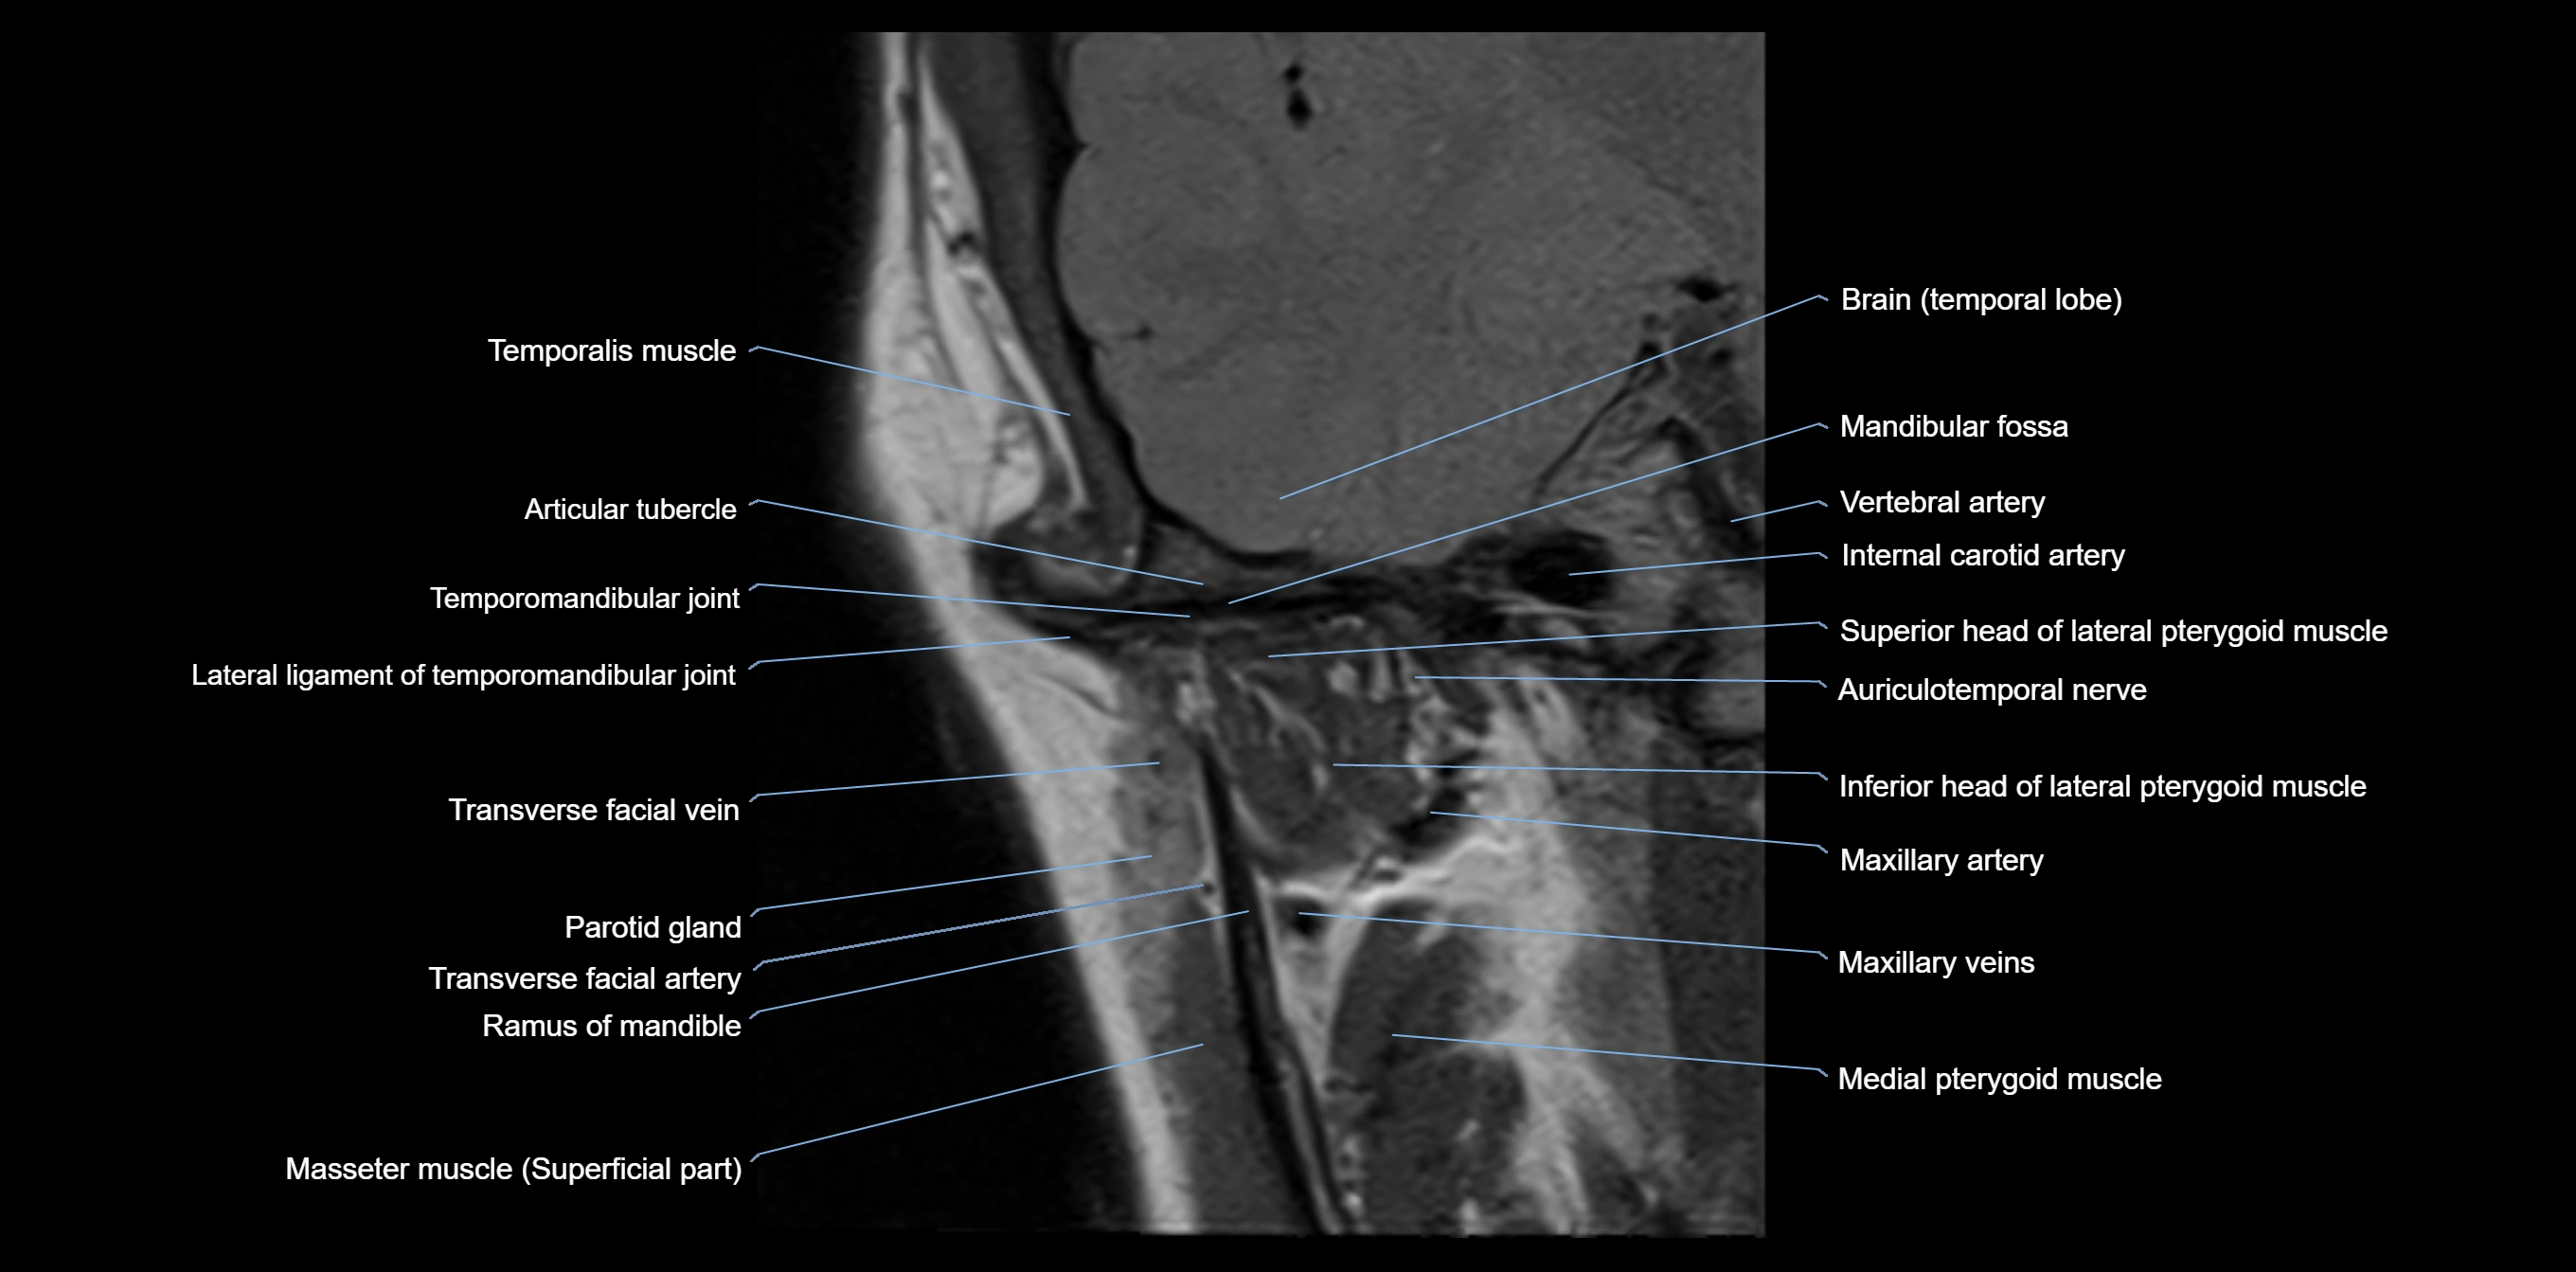

MRI appearance

T1-weighted images:

• Cortical bone: Low signal intensity

• Cancellous marrow: Intermediate to high signal depending on fatty content

• Teeth: Signal void structures

• Adjacent soft tissues: Normal gingiva and oral mucosa signal

T2-weighted images:

• Cortical bone and teeth: Low signal

• Marrow: Intermediate signal